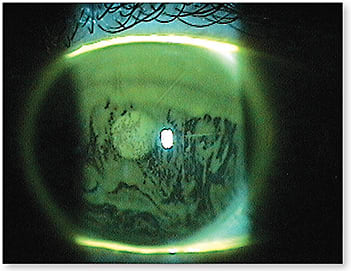

3. Show a Picture, and Make the Recommendation

A picture can go a long way, and showing a demo of contact lens surface dryness versus a smooth surface will help your patients understand how they may be successful (Figure 1). “I recommend lens X because of its hydration properties and high comfort rankings. This lens is prescribed to be worn on a (daily, extended, weekly, monthly, etc.) basis. Many patients dropped out of contact lenses previously because they were wearing the lenses for too long and without proper cleaning habits.”